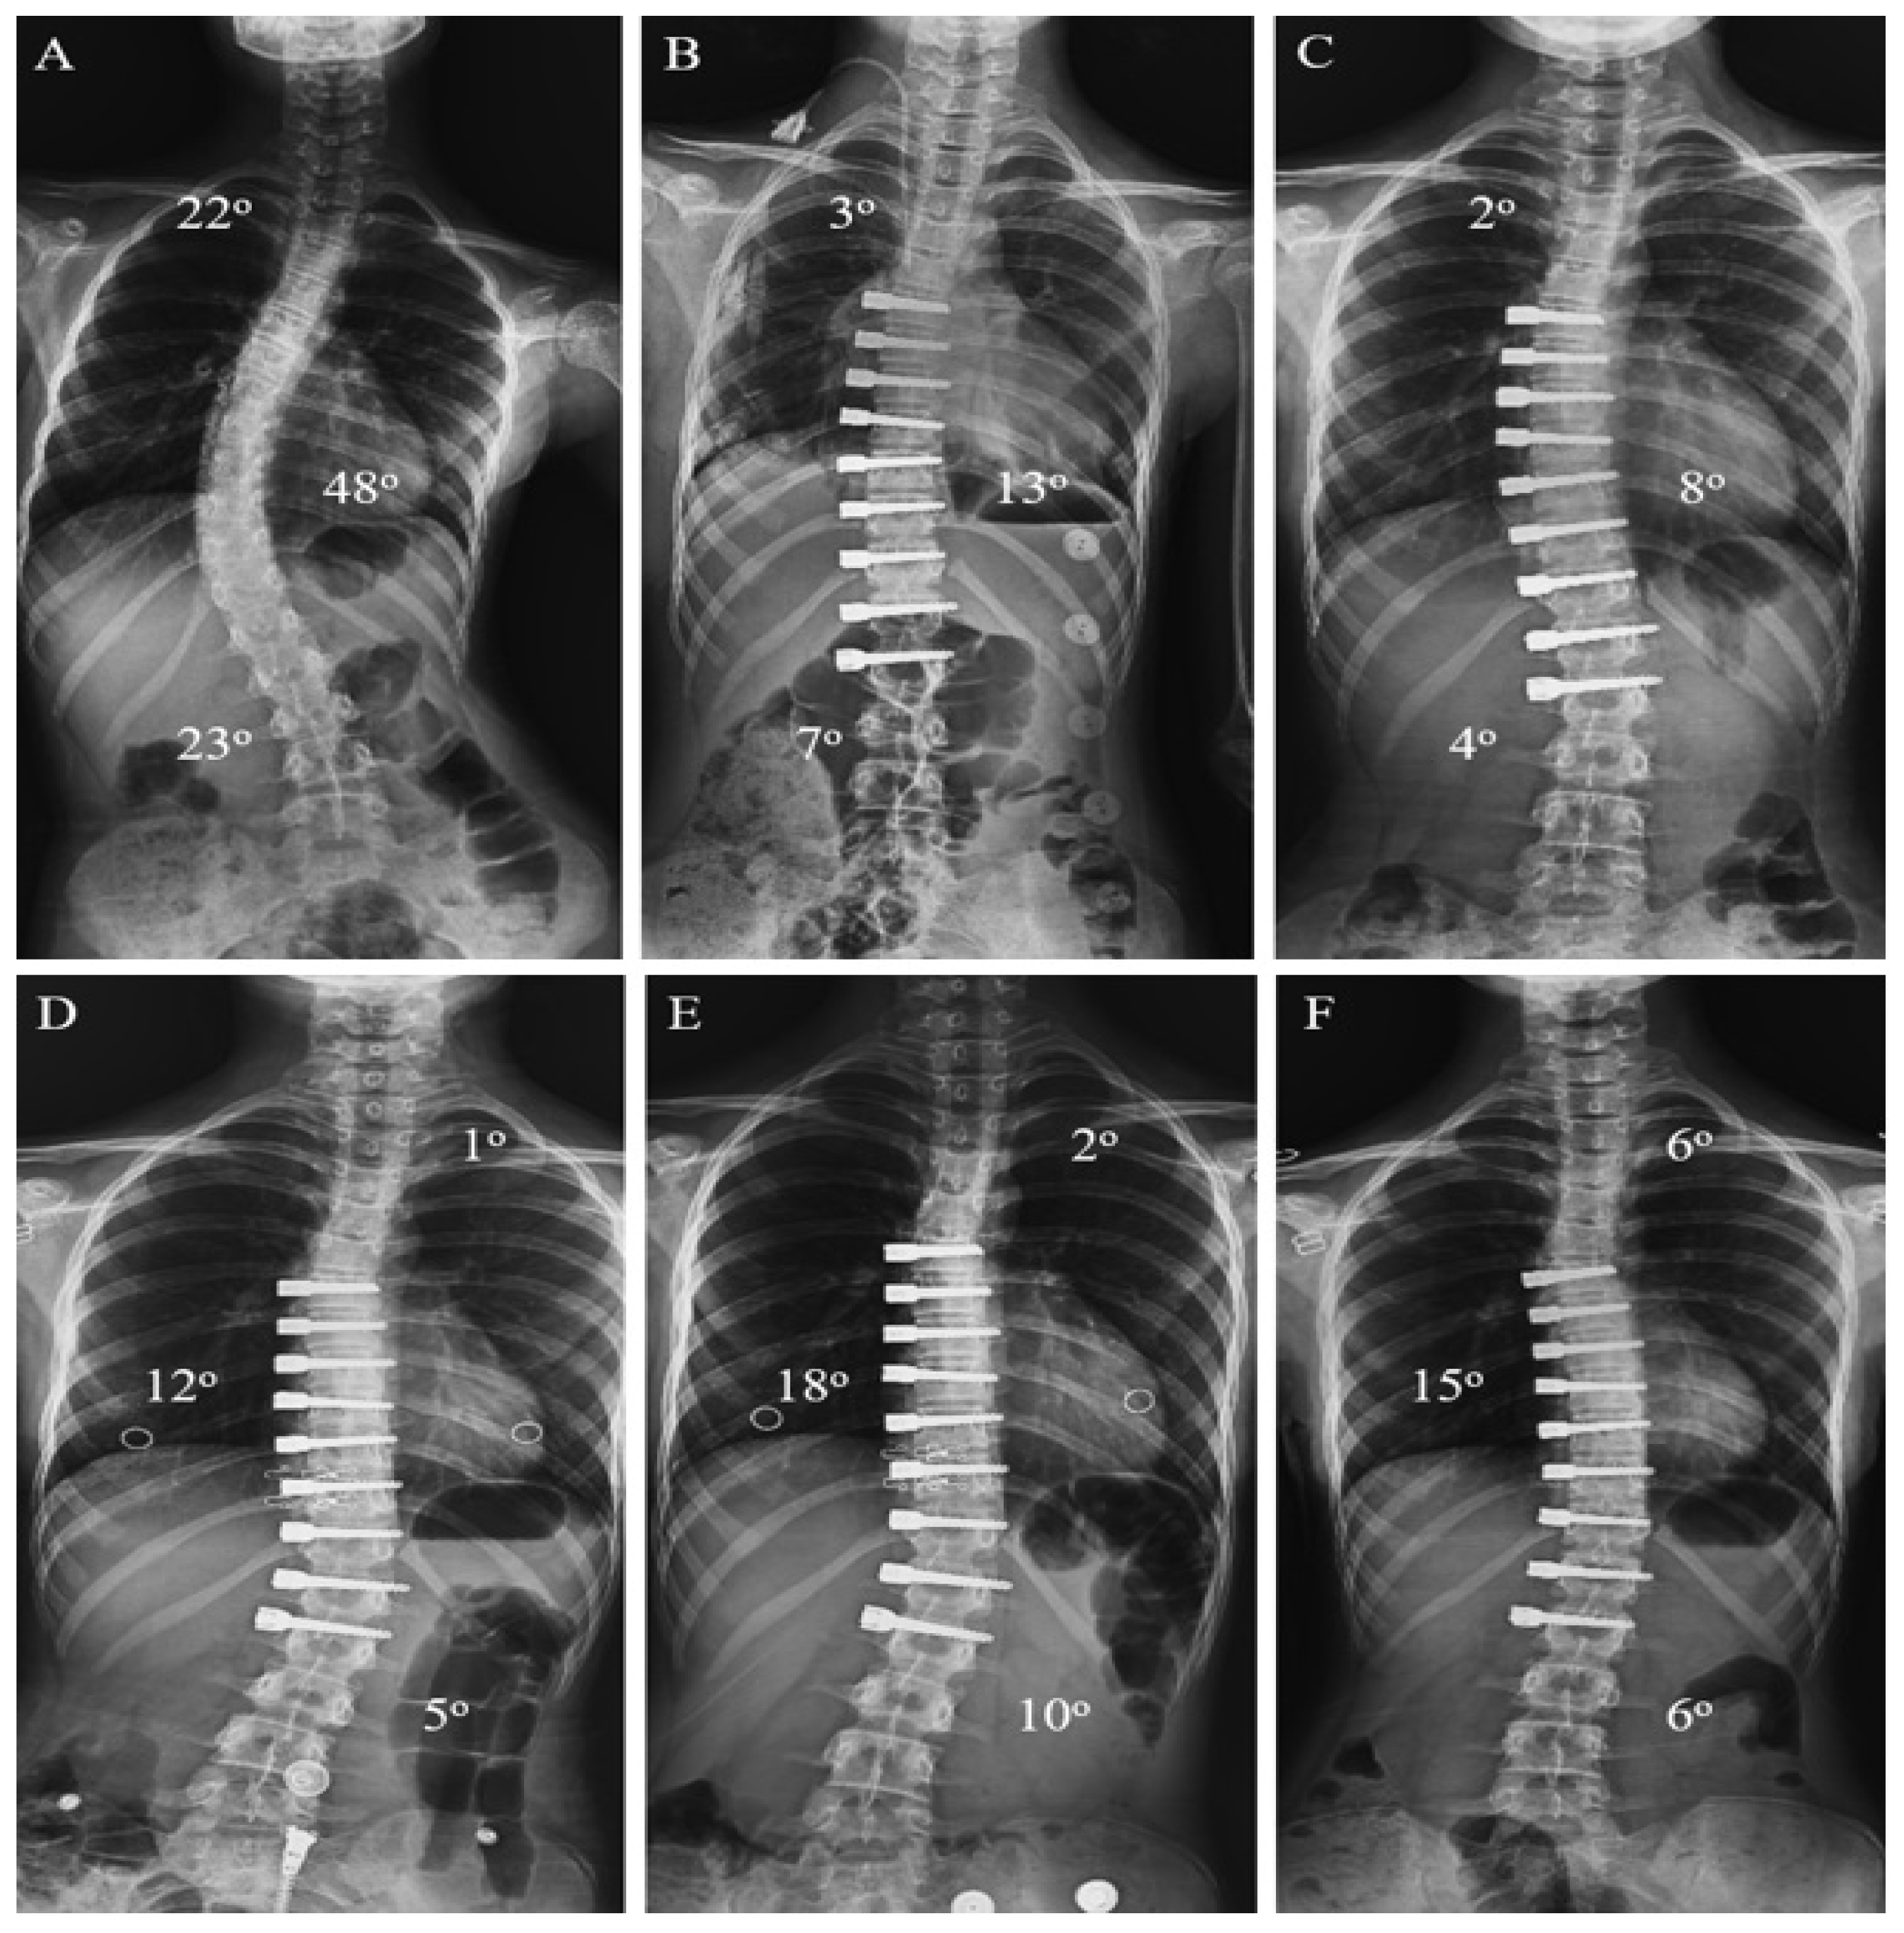

- In patients who underwent tethering, those with an LIV level at L2, L3, and L4 formed the thoracolumbar/lumbar AVBT group (Group 1). Patients who underwent AVBT in the thoracolumbar region and hybrid surgery, combining AVBT with thoracic fusion, were included in the AVBT group (Figure 1). The majority of thoracolumbar/lumbar AVBT cases underwent hybrid fusion procedures (9 out of 17, 52.9%).